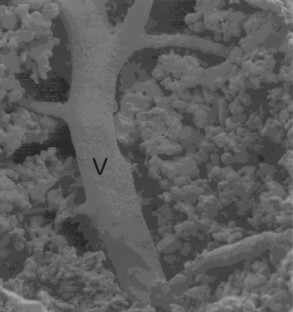

Interstitial laser hyperthermia (ILH) is an in situ ablative technique used to treat colorectal liver metastases. The relatively high recurrence of tumor after treatment by ILH may be related to incomplete destruction. Little is known about the effectiveness of ILH for destroying tumor microvasculature. The aim of this study was to define the changes to the microvascular architecture of tumors after treatment with ILH, specifically focusing on the completeness of tumor vasculature destruction. An intrasplenic induction model of liver metastases in 4- to 6-week-old male inbred CBA mice was used. Laser hyperthermia was applied to liver and tumor tissue using a bare optical quartz fiber from a Medilas Fibertom 4100 Nd:YAG surgical laser generator. The animals underwent microvascular corrosion casting of the livers immediately after application of ILH. Microvascular casts were then prepared and studied by scanning electron microscopy. ILH produced complete, uniform destruction of the tumor microvasculature with compete hemostasis. Blood flow in vessels larger than 100 μm diameter had a relatively protective effect, although ILH was able to overcome this barrier effectively by increasing the energy applied. ILH produces complete destruction of tumor microvasculature with hemostasis. The protective effect of blood flow in larger vessels can be overcome by the appropriate use of higher energy levels.

Fig. 3.